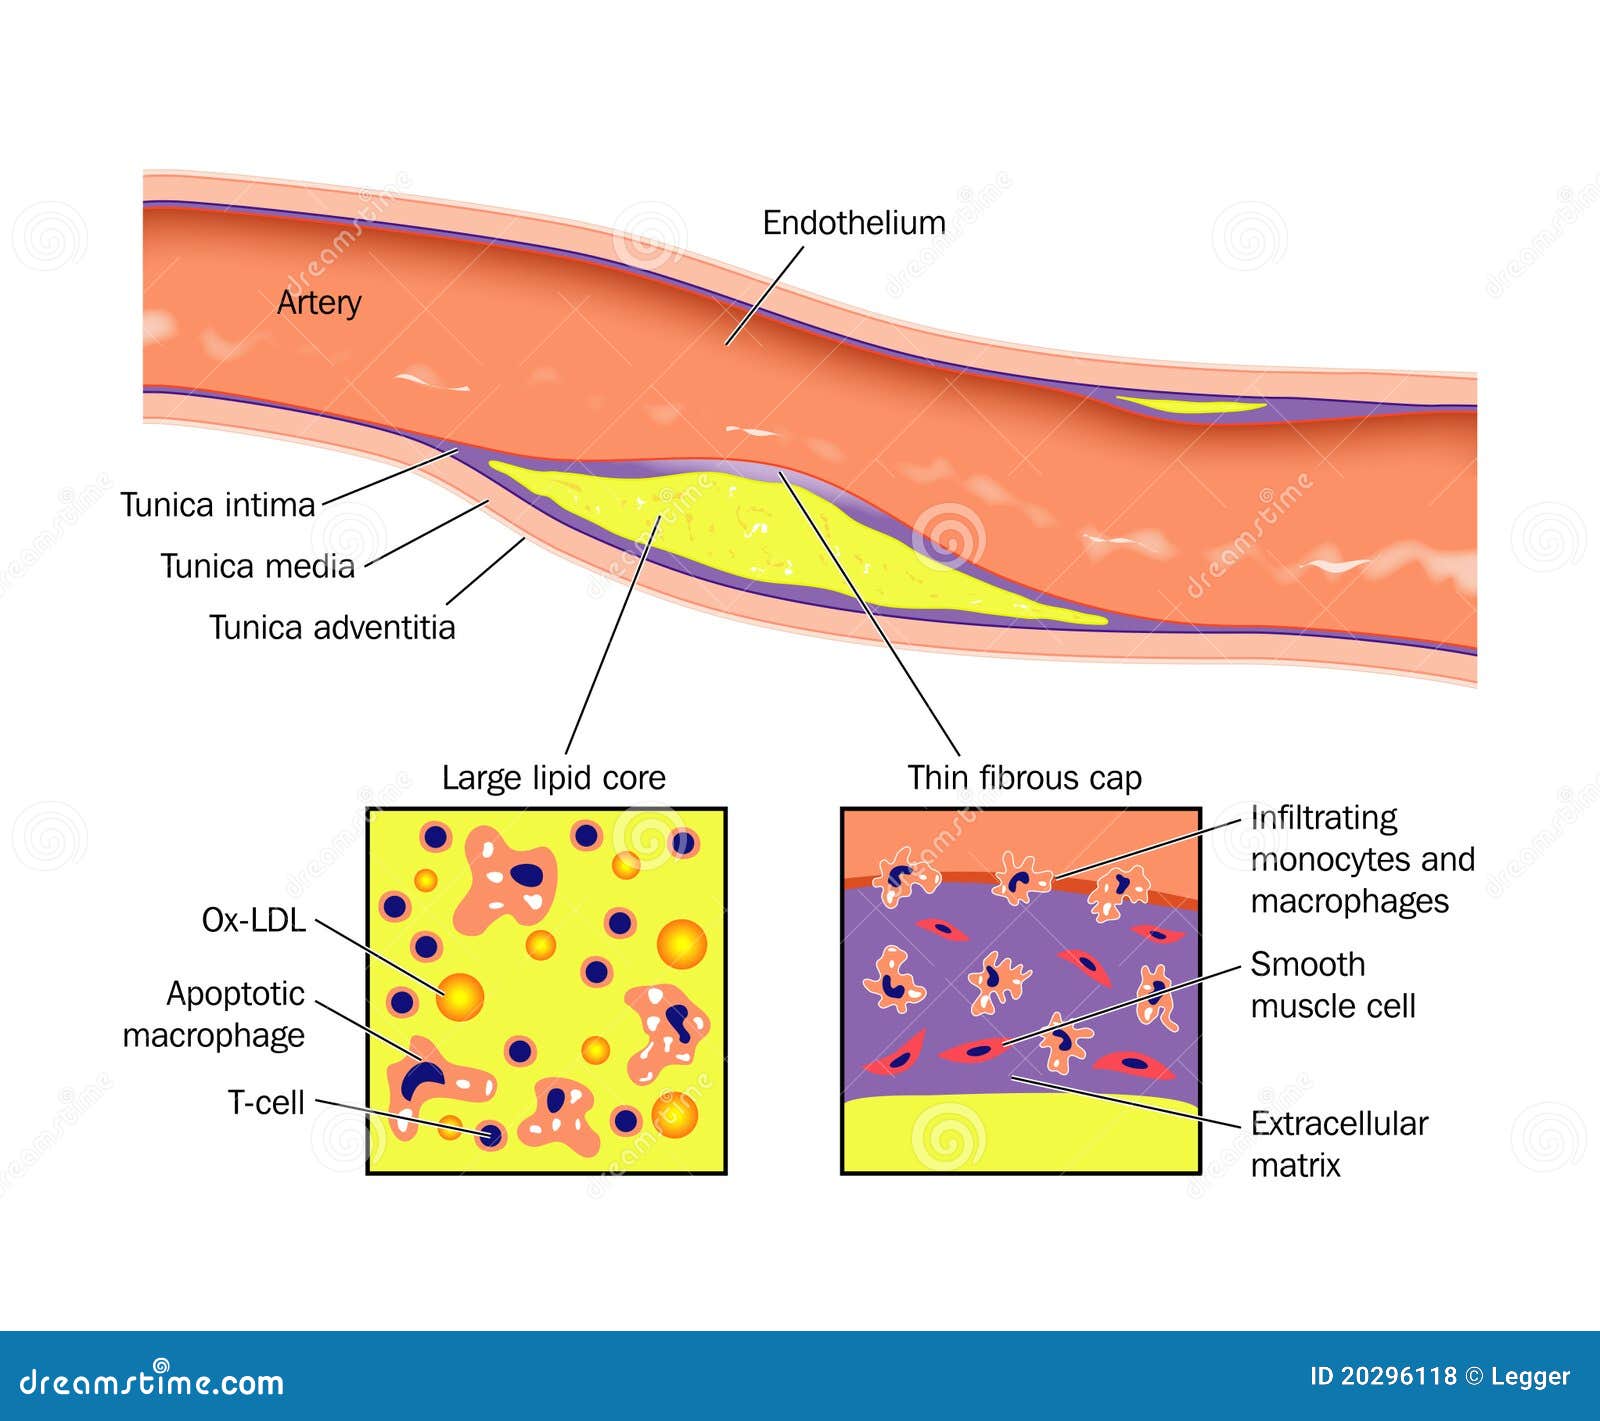

a deposit of plaque within the arterial wall

Artery Atheroma Plaque Vector Illustration | CartoonDealer.com #20296118